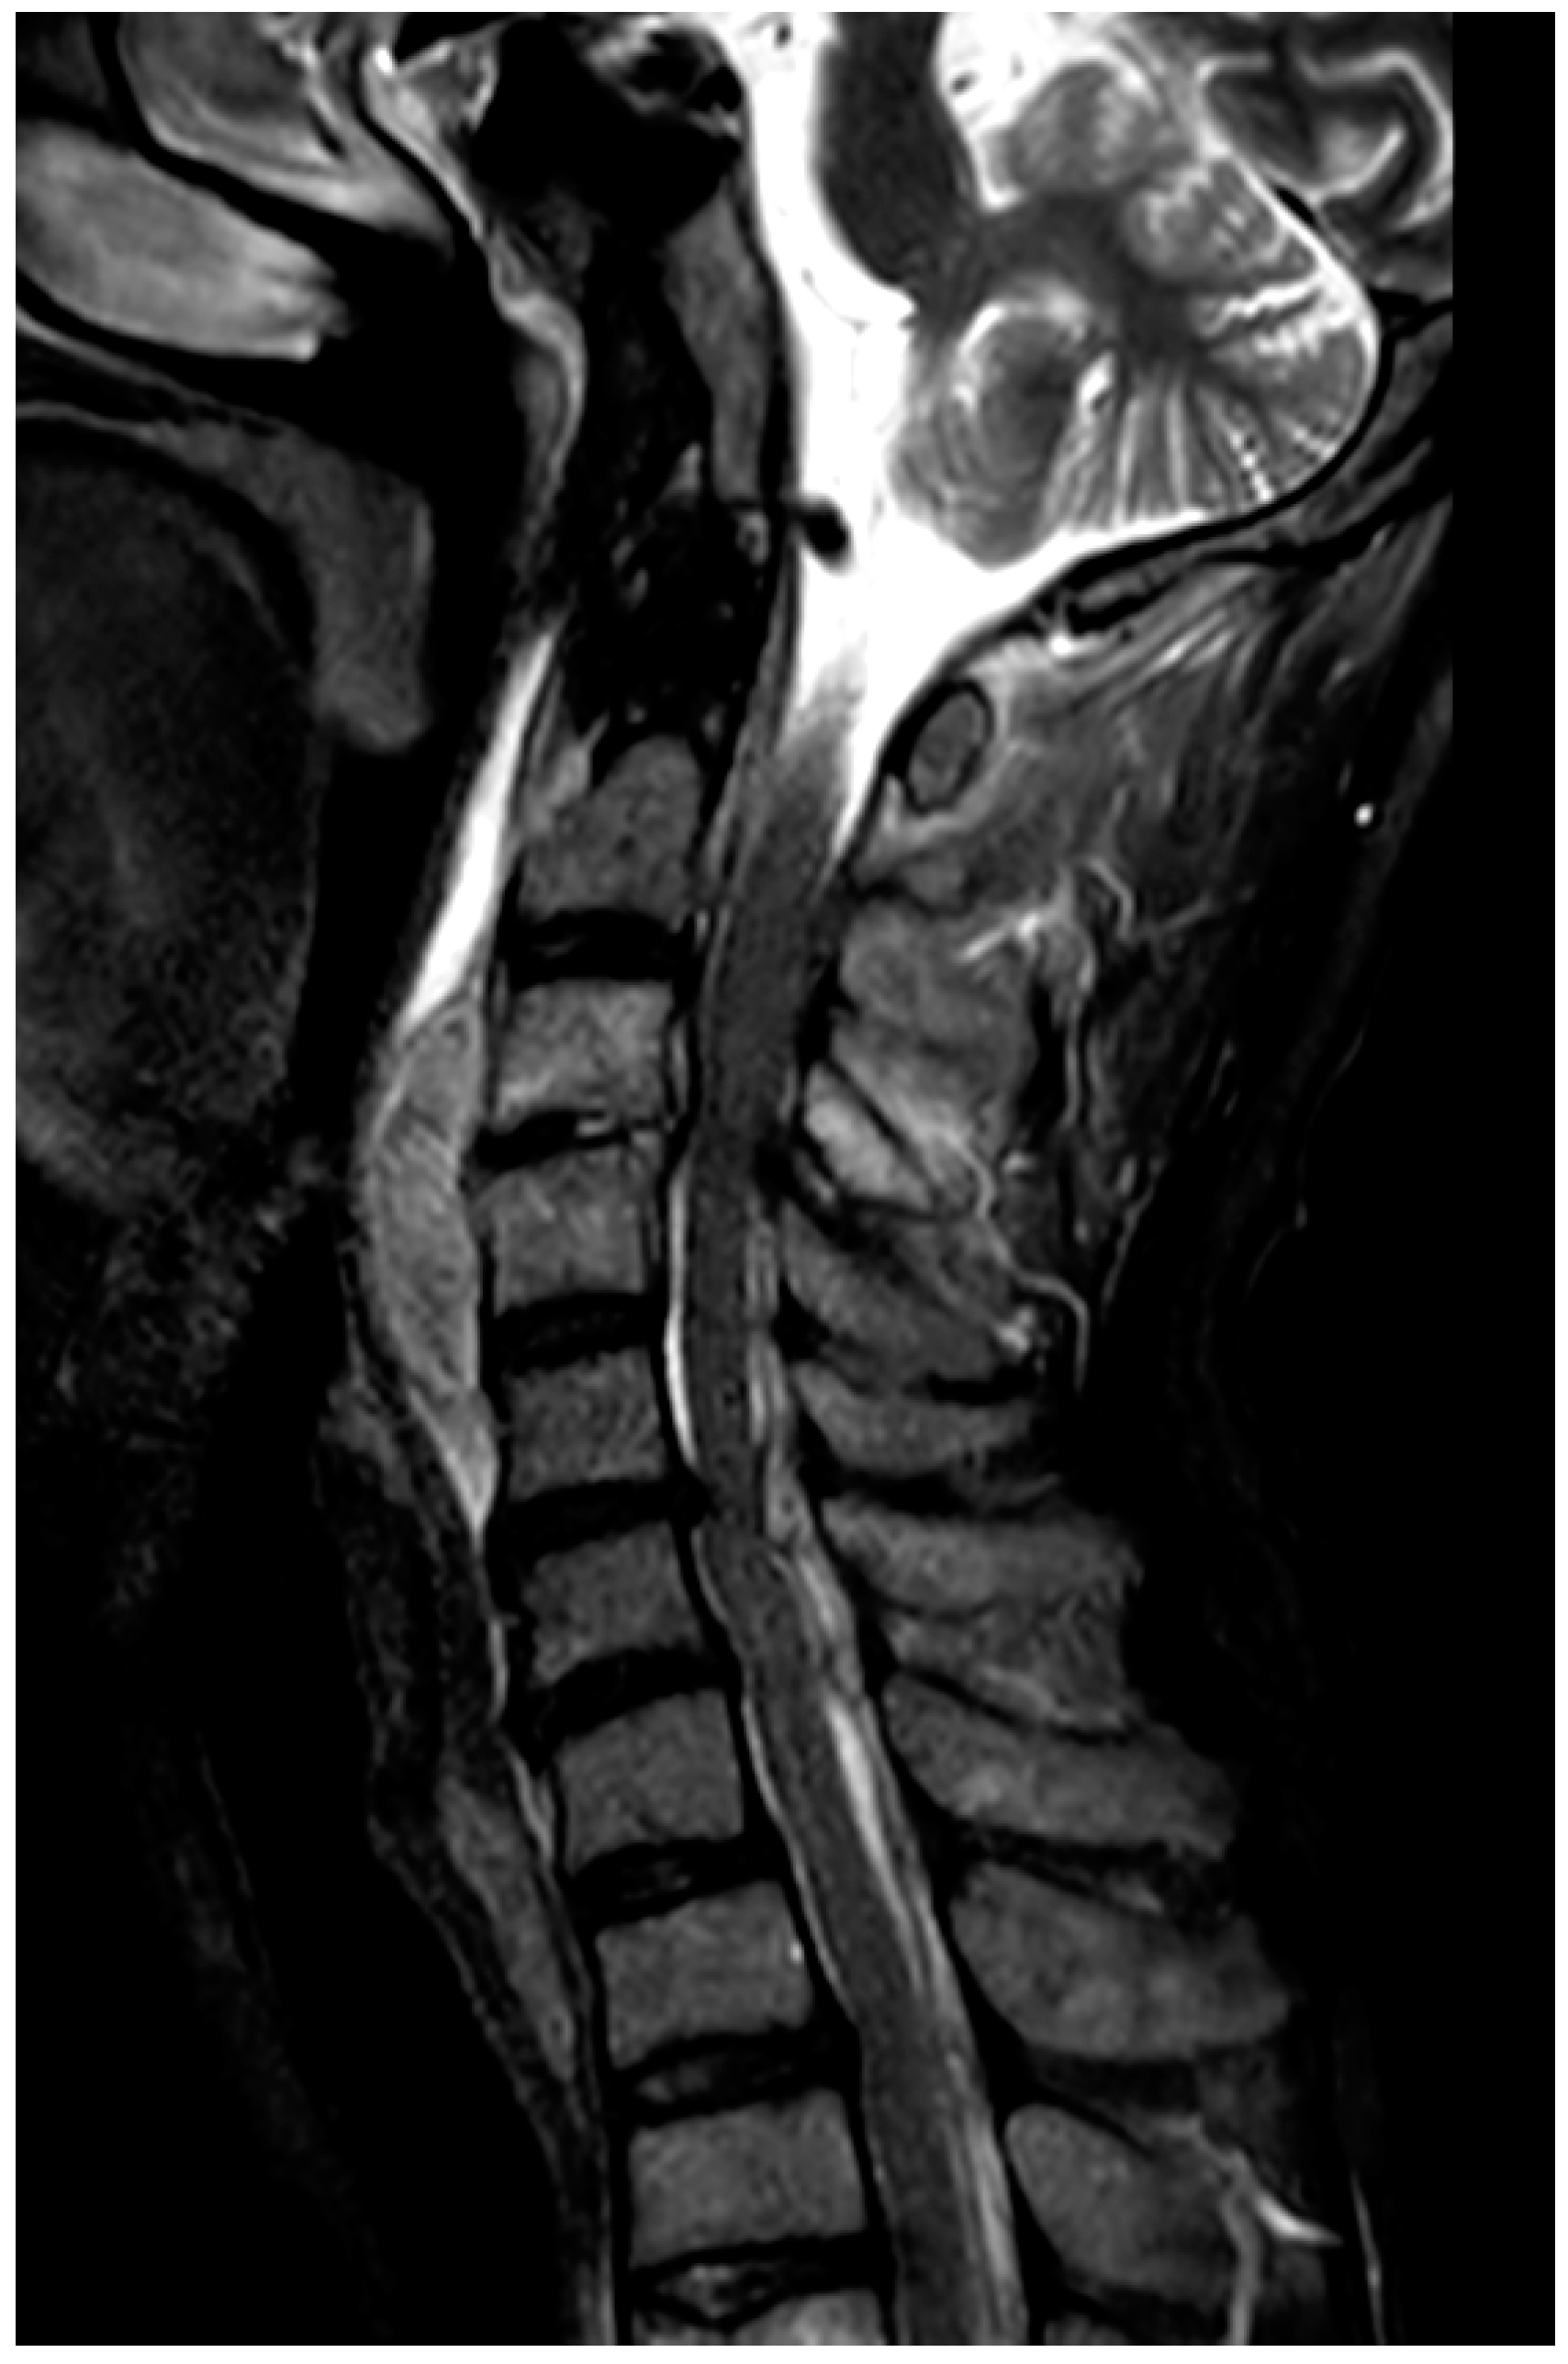

Adjunctive HBOT was initiated on day 14 (post-operative day 5), with a treatment protocol of 2.0 atm. absolute (ATA) for 60 min once daily for a total of 30 sessions. The regimen was under the recommendation of The Japanese Society of Hyperbaric and Undersea Medicine. Following HBOT, pain improved, inflammatory marker levels decreased, and motor function recovered. On day 23, MMT improved to shoulder joint abduction 1/2, elbow flexion 2/3, elbow extension 4/3, wrist flexion 4/4, wrist extension 3/3, finger flexion 4/4, and finger extension 4/4. MRI on day 23 showed anterior compression of the spinal cord at the C3–4, but spinal canal stenosis had not developed because laminectomy had been performed (Figure 3).

Figure 3. MRI T2 STIR on day 23. Although anterior compression at the C3–4 level has progressed, spinal canal stenosis has not developed because laminectomy had been performed.